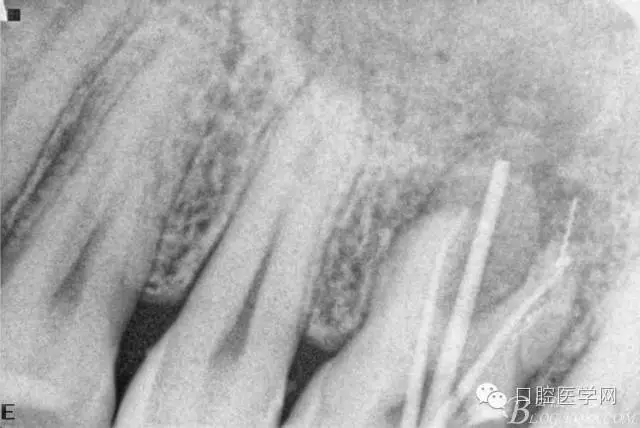

檢查26Ⅲ°松動(dòng)(頰舌向、近遠(yuǎn)中向、頜齦向)。X線片顯示根尖周彌漫性炎性陰影。

初診X線片